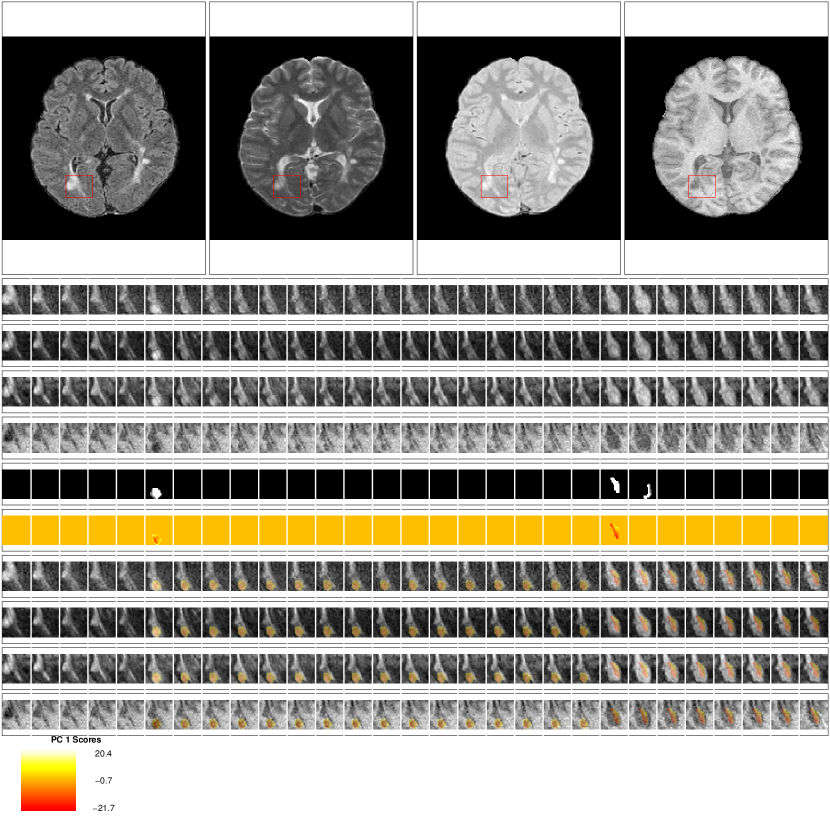

Examples of the set of evaluation images presented to the experts for each lesion are shown in Figures 8, 9, 10, and 11. The first row of the figures shows the full axial slice for the FLAIR, T2, PD, and T1 volumes that contains the largest number of voxels with abnormal signal intensity. The second through fourth rows show the entire collection of longitudinal scans for a box containing the abnormal signal intensity in the FLAIR, T2, PD, and T1 weighted volumes for this axial slice. The scans are displayed in chronological order, from first time point to last time point, from left to right. The fifth row shows the segmentation of the lesion and edema tissue within this box at each time point. The sixth row shows the score on the first PC for the voxels segmented as lesion tissue, displayed at the time of lesion incidence for each voxel. The seventh throughout tenth row shows the entire collection of longitudinal scans for the FLAIR, T2, PD, and T1 weighted volumes within this box with the score for the first PC overlaid on the images for each scan after lesion incidence. The last row shows the scale for the score on the first PC. The figures show examples of the four different ratings for the score on the first PC. Both raters rate the scans as either (1) failed miserably, (2) some redeeming features, (3) passed with minor errors or (4) passed.

Figure 9: Passed with minor errors: Rating of 3 for the score on the first PC. This scan received a rating of 3 for the score on the first PC from both raters. Both raters also gave a rating of 3 for the lesion segmentation. Note that at the 23rd time point new lesion voxels are segmented, but the score for the first PC is not produced for this time point, as the voxels did not meet the scanning criteria for being included in the analysis, which is described in detail in the Methods section of the paper.

Figure 10: Some redeeming features: Rating of 2 for the score on the first PC. This scan received a rating of 2 for the score on the first PC from both raters. Both raters also gave a rating of 2 for the lesion segmentation. The neuroradioloigst commented that this scan received a low rating because it was not clear that the segmented portion for time point 3 was lesion.

Figure 11: Failed miserably: Rating of 1 for the score on the first PC. This scan received a rating of 1 for the score on the first PC from both raters. Both raters also gave a rating of 1 for the lesion segmentation. Both raters commented that the low rating was because the lesion had existed in all time points and was not a new lesion.